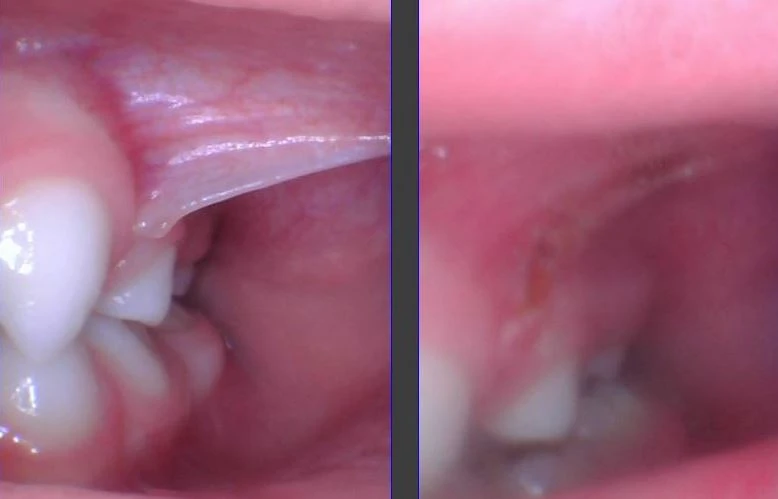

There are seven frena or folds of tissue in the mouth, and four of them are in the cheeks and are referred to as “buccal frena.” A frenum is considered a “tie” (tongue-tie, lip-tie, cheek-tie) when it causes a problem. Otherwise, it is a...